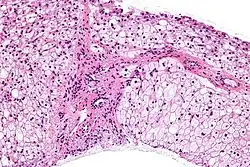

Glycogen storage disease in hepatocytes

SymptomsBiopsy shows either abnormal accumulation or deficit of glycogen

Diagnosis

Micrograph of glycogen storage disease with histologic features consistent with Cori disease. Liver biopsy. H&E stain.

Methods to diagnose glycogen storage diseases include history and physical examination for associated symptoms, blood tests for associated metabolic disturbances, and genetic testing for suspected mutations.[16][45] It may also include a non-ischemic forearm test, exercise stress test, or 12-minute walk test (12MWT).[45] Advancements in genetic testing are slowly diminishing the need for biopsy; however, in the event of a VUS and inconclusive exercise tests, a biopsy would then be necessary to confirm diagnosis.[45]